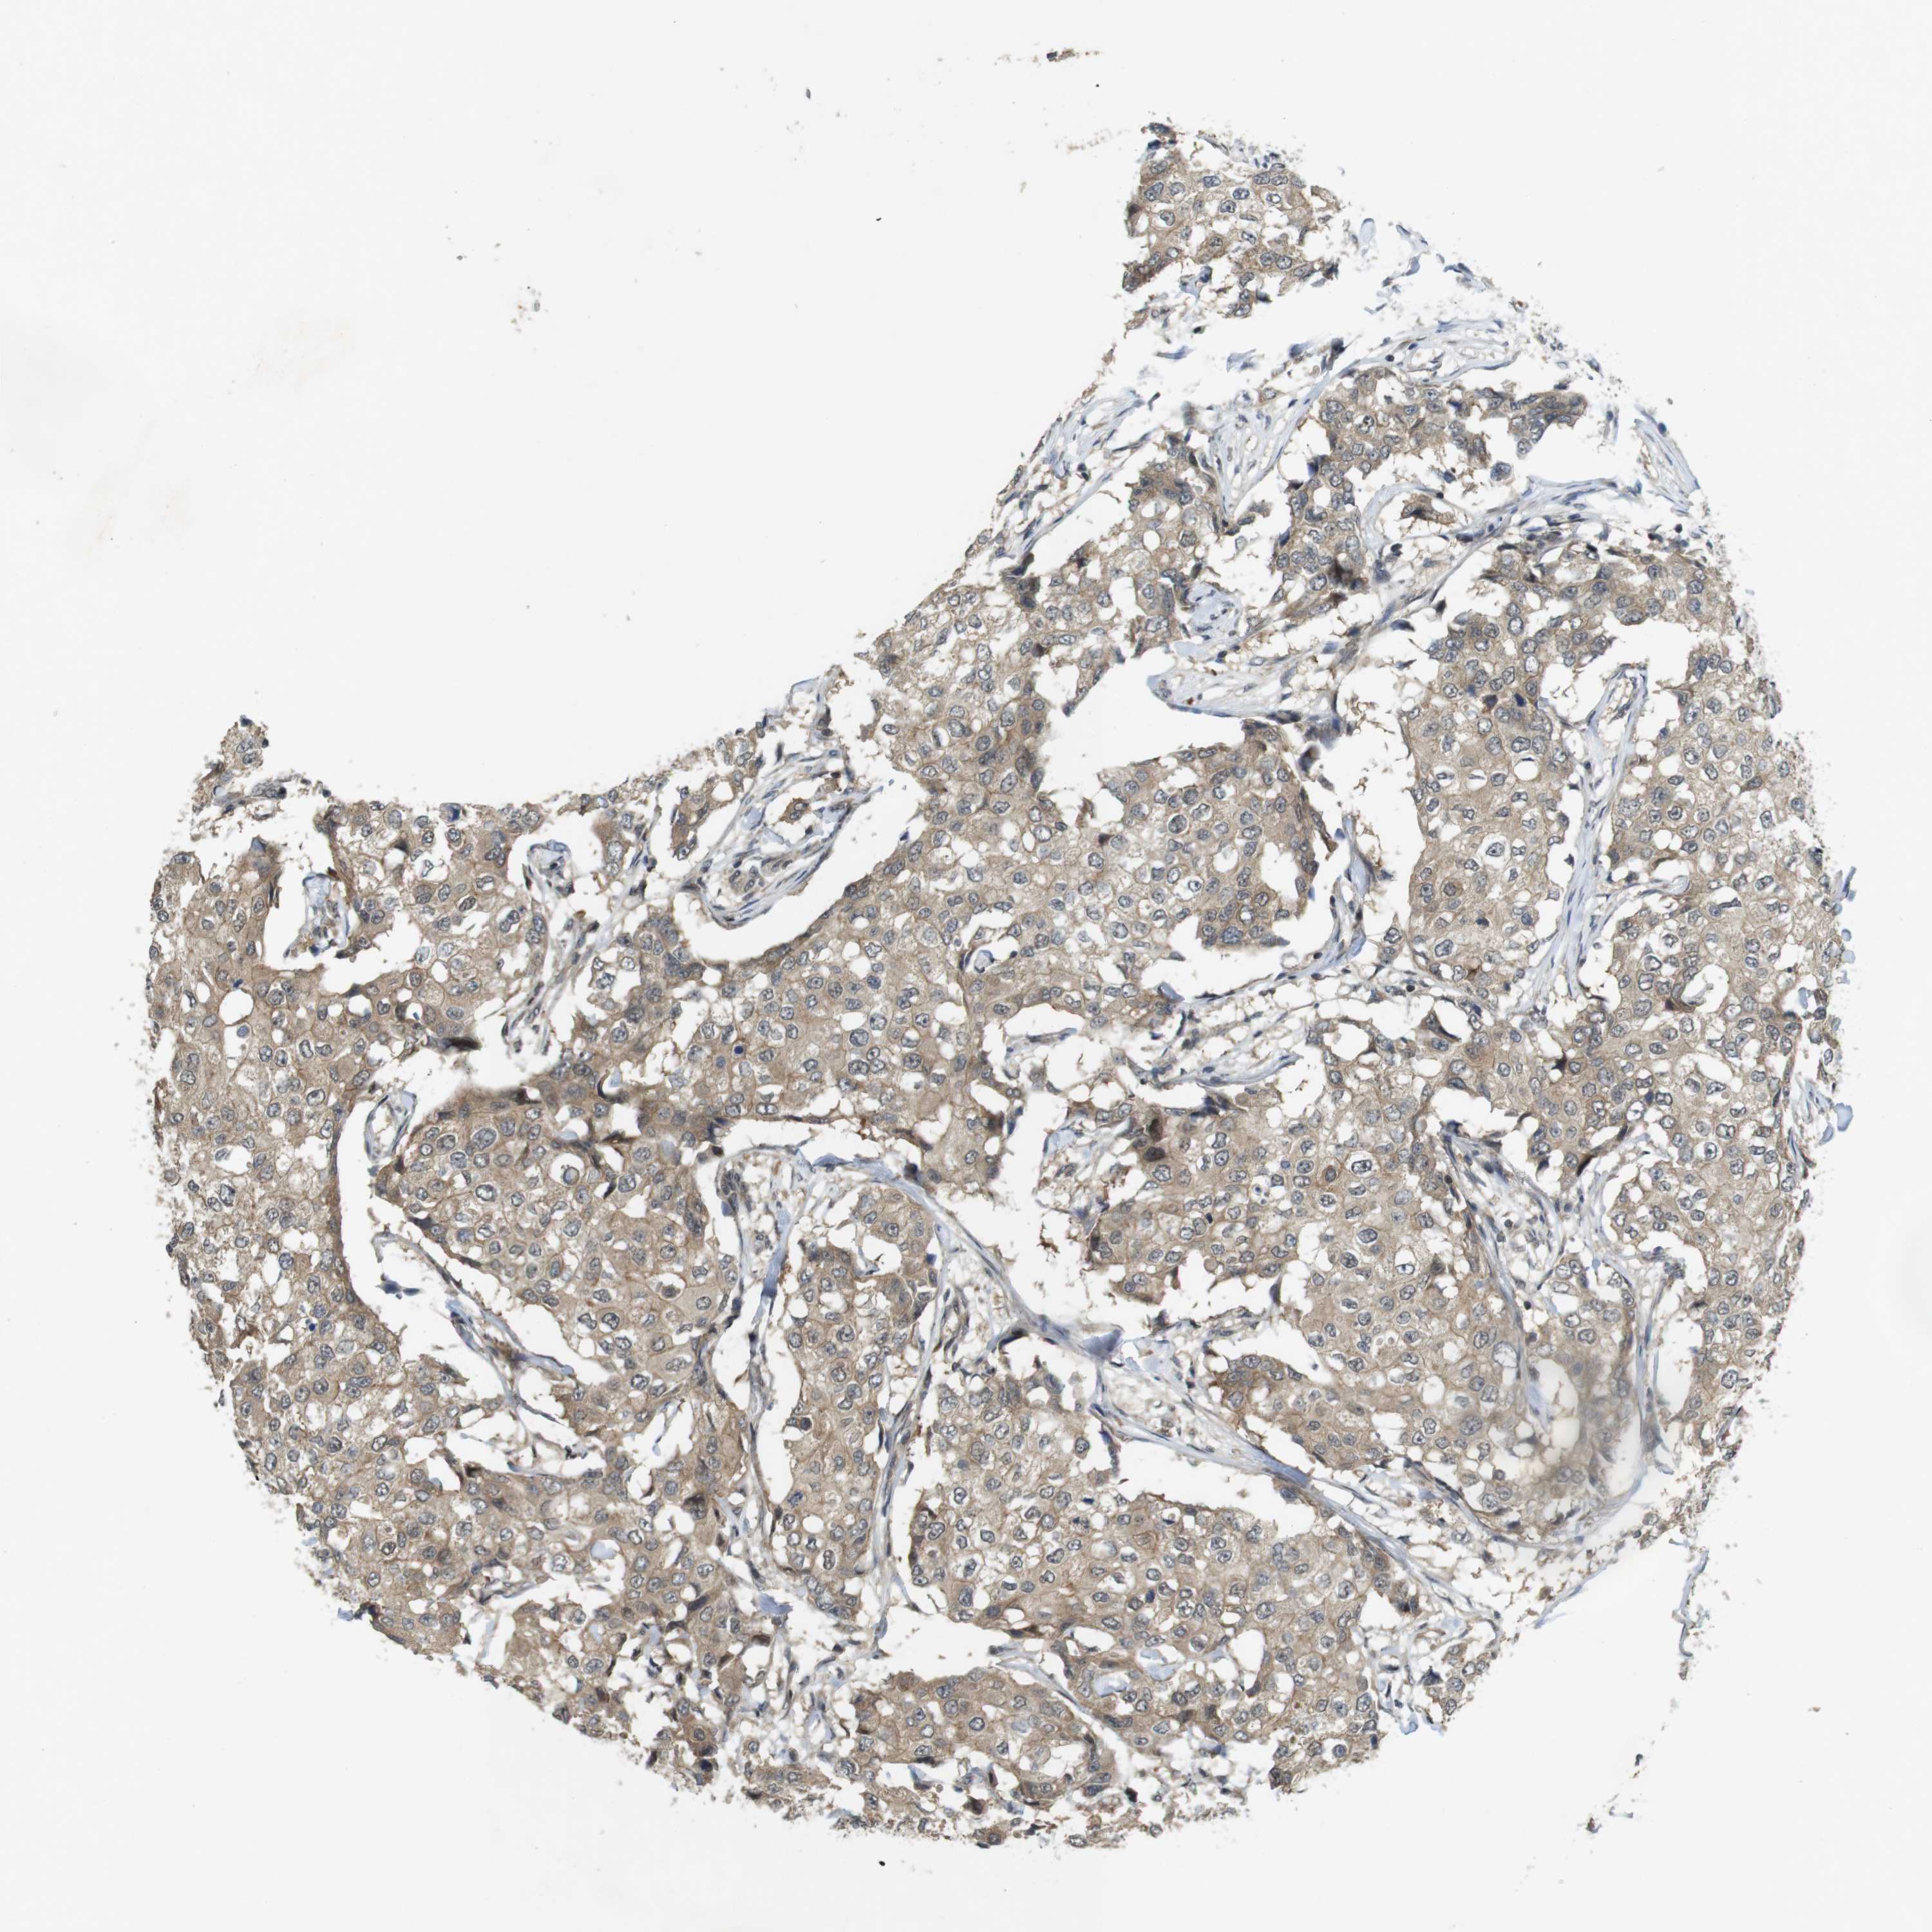

CANCER BREAST CANCER Show tissue menu

BRCA TCGA BRCA VALIDATION PROTEIN EXPRESSION